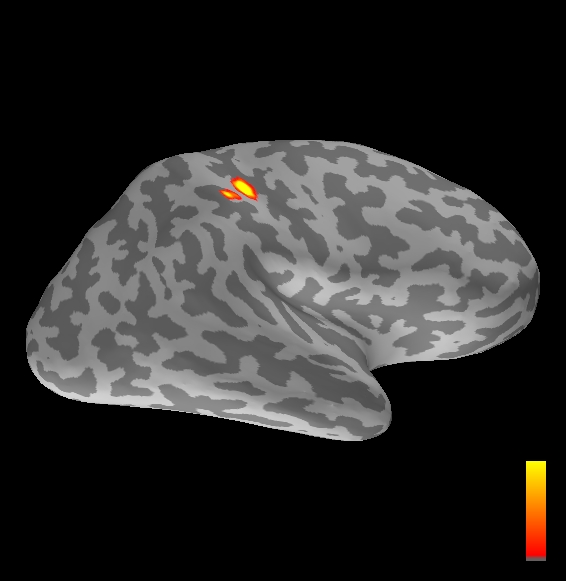

5.2 Results

We applied the ASMC sampler to MEG topographies taken from the above recordings by selecting specific time points according to the previous analysis; the parameter values in the algorithm were the same as those used for the analysis of synthetic data, with the only exception of the noise standard deviation , here estimated from the pre–stimulus interval. In order to validate the results of the ASMC, we also computed source estimates using three other methods: a PF, that approximates the posterior distribution for the current dipoles conditioned on the data up to the selected time point; dSPM, which is based on a distributed source model with an –prior, and consists in normalizing the Tikhonov regularized solution by the noise standard deviation; and sLORETA, which is similar to dSPM but is claimed to have a smaller localization bias. Figure 4 shows the results at , and ms after the stimulus onset. The results are visualized on a computer representation of the brain obtained by “inflating” the cortical surface: gray levels contain the anatomical information, light gray representing gyri and dark gray representing sulci; the activity estimate is coded in color scale, increasing from red to yellow. Importantly, this visualization allows activity in the sulci to be clearly visible; on the other hand, since neighbouring volumes may be moved apart by the inflation process, distinct activity regions are often due to underlying volumetric masses that are very close to each other.

Before describing the results, let us comment on the qualitative difference between the images produced by the ASMC sampler and the PF, on the one hand, and those produced by dSPM and sLORETA, on the other. First of all, we point out that all the quantities shown in the images of Fig. 4 are somehow related to the probability of activation at specific locations. Indeed, for both the ASMC and the PF we plot the approximation of the intensity measure (3.8); for any single grid point, this value can be interpreted as the probability of a dipole being at that location, while it integrates, over a given volume , to the mean number of dipoles within . As for dSPM, the represented quantity is a statistical value that is –distributed under the null–hypothesis of zero activity; as a direct consequence, it also yields a probability of activation, which is however not constrained to be dipolar. Similar considerations apply to sLORETA, although with a different statistical distribution. Importantly, the representation of the results is clearly affected by the setting of the visualization threshold. Owing to the explained differences between the methods, it seems reasonable to use a different value for each method. At the same time, since the plotted quantity is a probability of activation, it seems right to use the same thresholding for different time points. In this connection, the thresholds in Fig. 4 have been chosen by hand following the guidelines just outlined.

Using the same thresholding and parameters at different time points makes the four methods respond differently to the diverse intensities of the different sources. Whenever a stronger source is active, both sLORETA and dSPM will tend to produce widespread estimates, while weaker sources will be represented as small active areas. The behaviour of the ASMC and of the PF is the opposite: a stronger signal will lead to a precise localization of a dipolar source, and then to a focal marginal distribution for the location; a weaker signal will translate to higher uncertainty on the source position, and therefore a more widespread posterior map.

The phenomenon just described is indeed clearly visible in Figure 4. At ms, all the methods correctly identify the rather strong activation in the contra–lateral primary somatosensory cortex: the ASMC and the PF provide very focal maps, while dSPM and sLORETA provide compatible widespread estimates; dSPM also exhibits a more posterior peak which does not fit with the commonly agreed models of the response to median nerve stimulation; this may be due to the formerly described brain inflation.